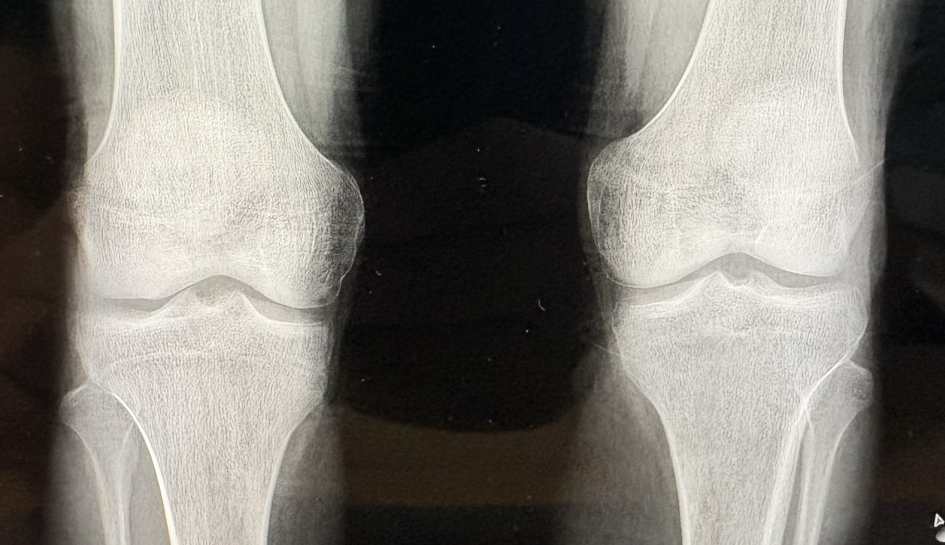

Pracownia RTG przy Zakładzie Radiologii Lekarskiej WIM-PIB informuje, że planuje wybrakować (zniszczyć) dokumentację medyczną pacjentów w postaci zdjęć rentgenowskich wykonywanych na kliszach z lat 2010-2011. Przeznaczone do zniszczenia oryginały dokumentacji można odbierać do dnia 10.11.2025 r.

Ogłoszenie o brakowaniu (niszczeniu) dokumentacji medycznej – zdjęć RTG